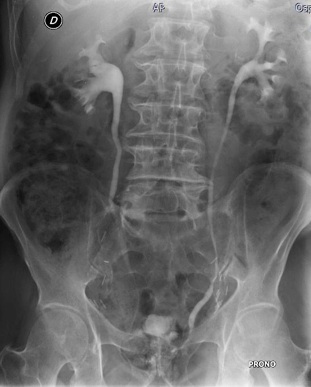

L'urografia è un esame radiologico che permette l'esplorazione e lo studio delle varie sezioni che compongono l'apparato urinario. Grazie all'urografia si ha un'esplorazione sia a livello morfologico che funzionale:

Si utilizzano come mezzi di contrasto composti organici idrosolubili triodati (uroangiografico), iniettati per via endovenosa a bolo o ad infusione lenta. A seguito di tale operazione si eseguono radiogrammi a tempi prestabiliti (basale, nei primi minuti dopo l'infusione, a seguire radiogrammi ogni 5 minuti), termine dell'infusione ultimo scanogramma, far urinare il paziente e scanogramma post-minzione.